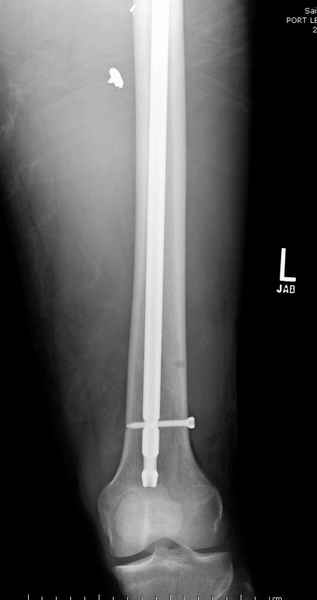

Учитывая, что больной получил травму не во время визита в церковь, и он является одним из представителем 40 миллионного “outstanding itizen”, без медицинской страховки, без работы в свои 39 лет, и без надлежающей ортопедической дисциплины у которого отсутсвует страх стрессового перелома, было рекомендовано оперативное лечение: профилактическое антеградное интрамедуллярное штифтование.

Выглядит агрессивно, и обычно госпиталь, беря финансовые расходы, остается в убытке, но мы всё же посчитали, что издержки от штифтования намного меньше, чем возможные финансовые и моральные издержки лечения таких больных, но с осложнением.

Методика штифтования при отсутствии большой зоны перелома как при онкологических профилактических штифтованиях, расверливание интрамедуллярного канала проводим с предварительным наложением дополнительного дренажного отверстия в дистальном отделе бедра (в данном случаи в канале оставили 6.5 мм канюлированный шуруп), иначе при создании давления в канале во время сверления имеется опасность эмболизации легочной артерии тромбом.